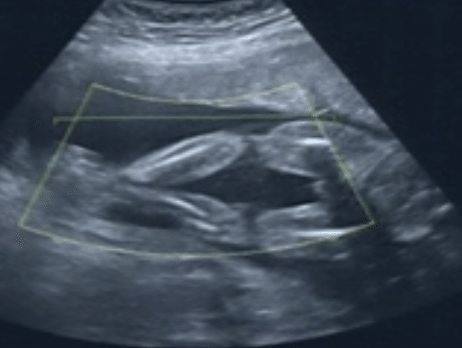

宝妈们,帮我分析一下四维彩超图片是男宝还是女宝 点击展开 匿名用户 2015-02-07 18:50 满意回答 是男孩。我们这200元就给说。 曾雪瑶_uffg 2015-02-07 19:00 宝宝知道提示您:回答为网友贡献,仅供参考。 相关问题 这里有一张四维彩超图片,懂行的进来看看是男宝还是女宝~ 有没有宝妈们怀男宝和女宝时孕期反应是一样的 宝妈猜猜我们家的宝宝像男宝还是女宝?这是20+2的肚子!